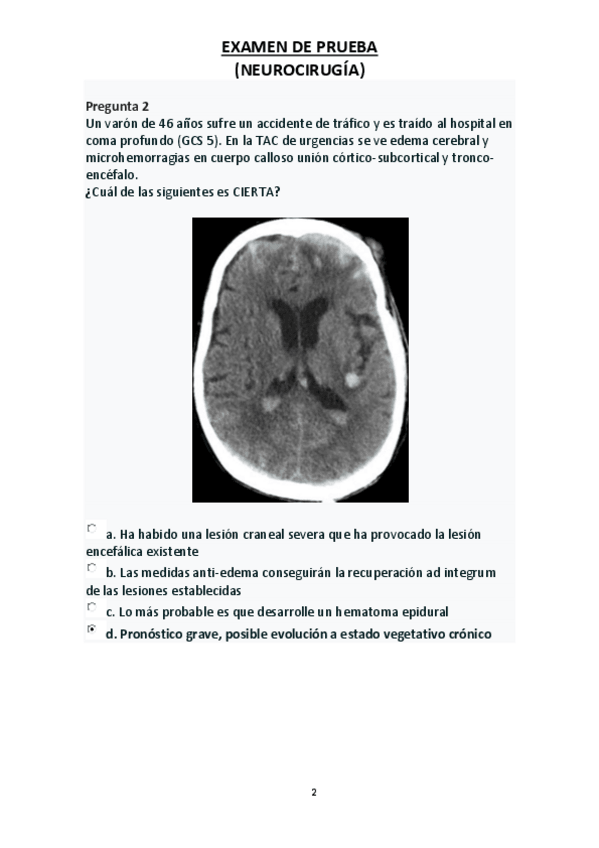

EXÁMENES NEUROCIRUGÍA. PASADOS por IA

Exámenes de Neurocirugía pasados por IA

He publicado nuevos apuntes de 5º Patología del sistema nervioso: Examen-de-prueba-NEUROQx.pdf

209 páginas